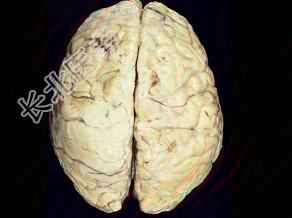

- 单项选择题观察图片所示病理,流脑脑膜炎期的病变特点下列说法正确的为 ( )

A、早期能发生脑室孔阻塞

B、病变主要部位在软脑膜及蛛网膜

C、脑实质无炎症

D、颅底部炎症粘连可导致脑神经损害

E、硬脑膜水肿